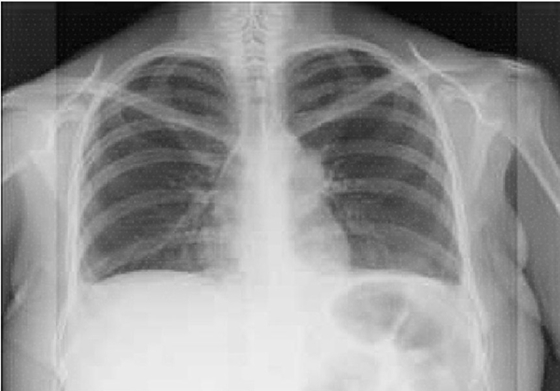

La paciente fue enviada 5 meses después a gastroenterología para descartar cáncer gástrico. Como parte del protocolo prequirúrgico para la realización de endoscopia se observó ensanchamiento mediastinal en la telerradiografía de tórax (Figura 1). El reporte histopatológico de la biopsia de estómago fue atrofia, engrosamiento de la capa muscular e infiltrado linfoplasmocitario, sin cambios compatibles con cáncer. En la tomografía toracoabdominal (Figura 2) se confirmó la tumoración en mediastino anterior. Fue sometida a toracotomía, donde se identificó un tumor mediastinal anterior de 8 a 10 cm, clasificado como timoma B1, con invasión a pericardio parietal y rama pulmonar izquierda.